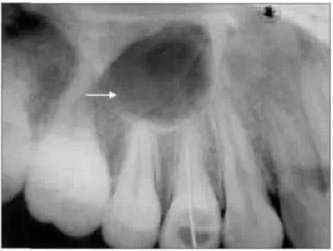

臨床上,由于拍攝角度的變化,患者頜弓大小不同、解剖異常等情況的存在,常會(huì)在正常情況下拍攝出異常的牙片。如出現(xiàn)上頜竇位置不同(見(jiàn)圖1、2),牙齒形態(tài)異常、根管變異等。據(jù)文獻(xiàn)報(bào)道,由于拍攝X線片操作的原因,口內(nèi)拍攝牙片約有9.68%的失誤;尖牙-前磨牙區(qū)失誤最多,可占總失誤的70.6%。為了防止出現(xiàn)誤診,醫(yī)師需要非常熟悉牙齒和周圍組織的解剖結(jié)構(gòu),并結(jié)合臨床檢查情況進(jìn)行判定;如所拍攝的牙片出現(xiàn)可疑情況,需更換角度,重新拍攝。

典型病例2,患者為女性,50歲。1個(gè)月來(lái),每晚睡后1 h左右,右側(cè)牙齒出現(xiàn)陣發(fā)性疼痛,并向耳顳部放射。口腔檢查,17缺失,16和46、47有充填物,密合,未探及牙周袋,15已作根管治療;冷熱診反應(yīng)正常。X線牙片示:16遠(yuǎn)中根吸收至根尖(圖8左箭頭示);46、47根尖無(wú)明顯陰影,46根分叉陰影(圖8右箭頭示)。拔除16,46、47行根管治療后,癥狀仍未改善。請(qǐng)神經(jīng)科會(huì)診,未見(jiàn)異常。復(fù)查牙片,見(jiàn)46、47根尖近下齒槽神經(jīng)管處密度較高,拍攝上下頜全景片,見(jiàn)46、47根尖下方有一約3 cm×4 cm密度增高區(qū);拍攝牙CT片,可見(jiàn)密度增高影和下齒槽神經(jīng)管重疊(圖9中圓圈示)。做下齒槽神經(jīng)管減壓術(shù)后癥狀消失。